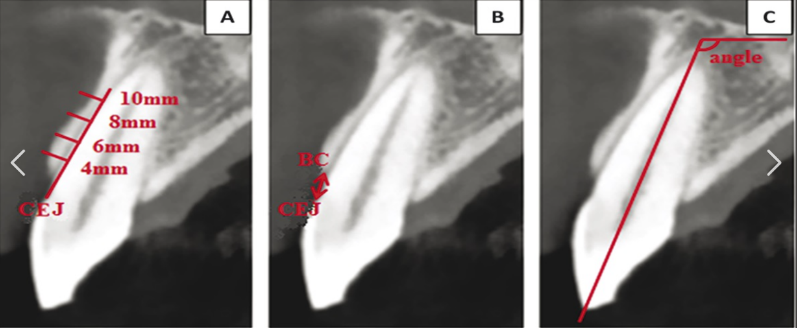

- Apico-coronal positioning:

- Place bone-level implants 2-3mm subcrestally in the esthetic zone

- Adjust depth based on implant system recommendations

- Consider soft tissue thickness for proper emergence profile development

- Implant angulation:

- Maintain angulation within 0-15 degrees of ideal axis to minimize off-axis forces

- Align implant with prosthetic requirements for screw-retained restorations

- Avoid extreme angulations that necessitate custom abutments